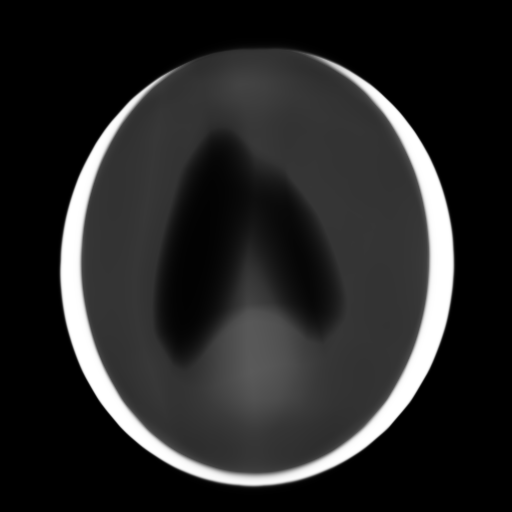

2D computed tomography (CT). In CT, we observe integral projections of a density field instead of direct measurements. In our 2D CT experiments, we train an MLP that takes in a 2D pixel coordinate and predicts the corresponding volume density at that location. The network is indirectly supervised by the loss between a sparse set of ground-truth integral projections and integral projections computed from the network’s output. We conduct experiments using two datasets: procedurally-generated Shepp-Logan phantoms [36] and 2D brain images from the ATLAS dataset [21].

In computed tomography (CT), we observe measurements that are integral projections (integrals along parallel lines) of a density field. We construct a 2D CT task by using ground truth resolution images, and computing 20 synthetic integral projections at evenly-spaced angles. For each of these images, the supervision data is the set of integral projections, and the test PSNR is evaluated over the original image.

We use two datasets for our 2D CT task: randomized Shepp-Logan phantoms [36], and the ATLAS brain dataset [21]. For each dataset, we perform a hyperparameter sweep over mapping scales on 8 examples. We found that scales and work best for the Shepp dataset and and work best for the ATLAS dataset. In Table 5, we report model performance using the optimal mapping scale on a distinct set of 8 images.